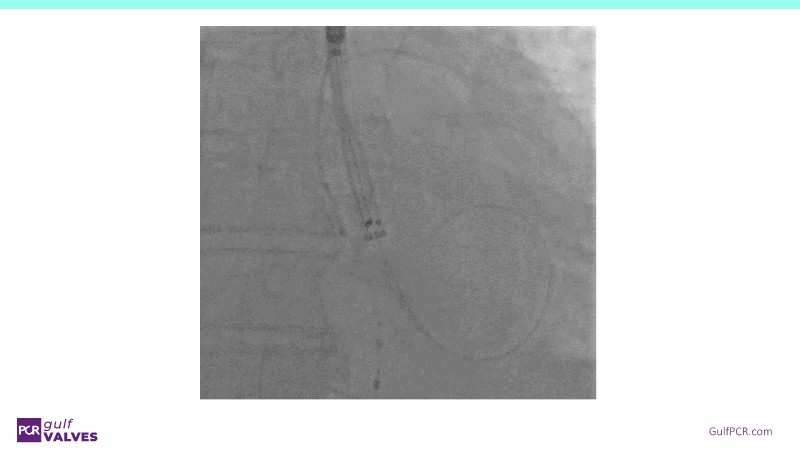

Discover a selection of cases showcasing the key features of the Navitor Valve System and its clinical applications. This session explores auxiliary access, the use of Navitor in alternative access and complex PCI, its performance in challenging peripheral anatomies, and innovative outcomes with the Vantage 30D system.